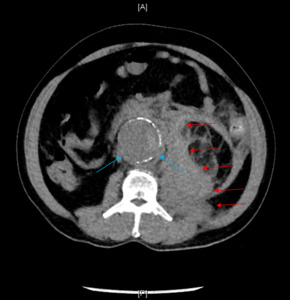

Upon arrival at the main ED, the patient was noted to be alert and oriented, ill appearing, tachycardic, and tachypneic. Upon further questioning, the patient stated he started having left lower quadrant abdominal pain and left flank pain that evening. The patient reiterated that the injury was sustained via a fall in a bathroom following sudden dizziness. He denied sustaining a head injury or syncope. Repeat vital signs showed HR 135bpm, RR 39bpm, BP 102/76 mmHg, SaO2 100% while on 4 LPM oxygen via a nasal cannula, and a temperature of 36.10C. In the repeat physical exam notable abdominal distention without tenderness was noted. Computed Tomography (CT) of the abdomen and pelvis was ordered for further evaluation. Given the patient’s low glomerular filtration rate, intravenous contrast was not utilized due to institutional protocol. Therefore, a non-contrast abdominal/pelvic CT was ordered to evaluate for abdominal distention and a ventilation-perfusion scan was ordered to evaluate for pulmonary embolism (PE). Repeat lactic acid was measured to be 6.0 mmol/L. Abdominal/pelvic CT showed a ruptured 5.5 cm infrarenal abdominal aortic aneurysm with peri-aortic and left retroperitoneal hemorrhage (Figure 1). Vascular surgery was immediately consulted, and the patient was taken to the operating room for emergent endovascular aneurysm repair (EVAR). The Intensive Care Unit (ICU) was also consulted for patient admission and further management. Post-operatively, the patient developed hyperglycemia, lactic acidosis, non-STEMI due to demand ischemia, acute respiratory distress syndrome (ARDS), intra-abdominal hypertension, acute blood loss anemia, acute kidney injury, and systemic inflammatory response syndrome (SIRS). The patient was aggressively treated, and was eventually able to be weaned off the ventilator, extubated and downgraded from the ICU after six days. After six more days of medical management, the patient was discharged in stable condition on hospital day 12 to a skilled nursing facility with a vascular surgery follow-up.